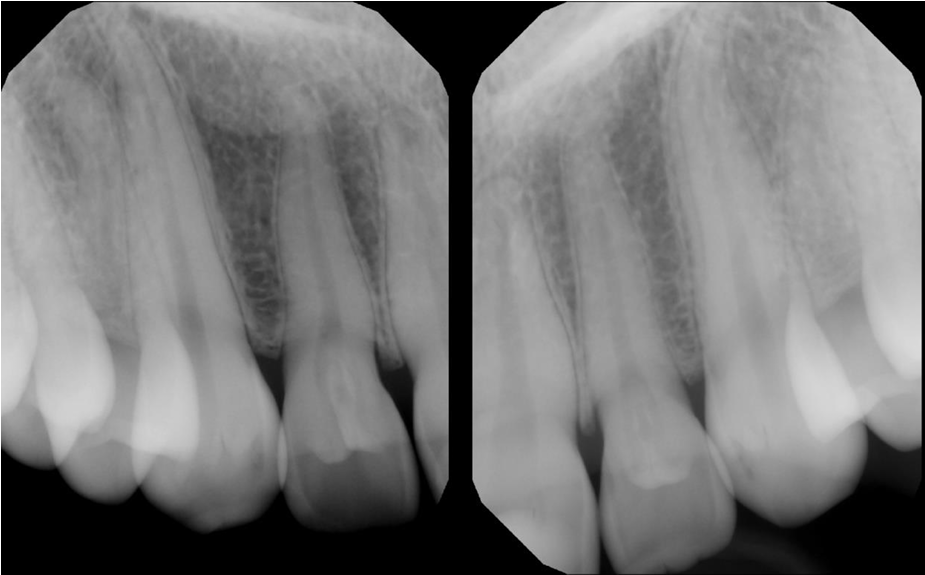

Radiology Case 2

A 16-year-old female came in for a routine examination, upon clinical examination, periapicals of the maxillary anterior region were ordered.

Radiographic findings: Radiographs reveal well-defined radiolucent infoldings within the crown of the lateral incisors, outlined by a thin radiopaque enamel/dentin border. The invaginations extend almost up to the root.

Interpretation: Dens invaginatus in the maxillary lateral incisors

Treatment: In the absence of periapical inflammatory signs, prophylactic sealing is recommended.